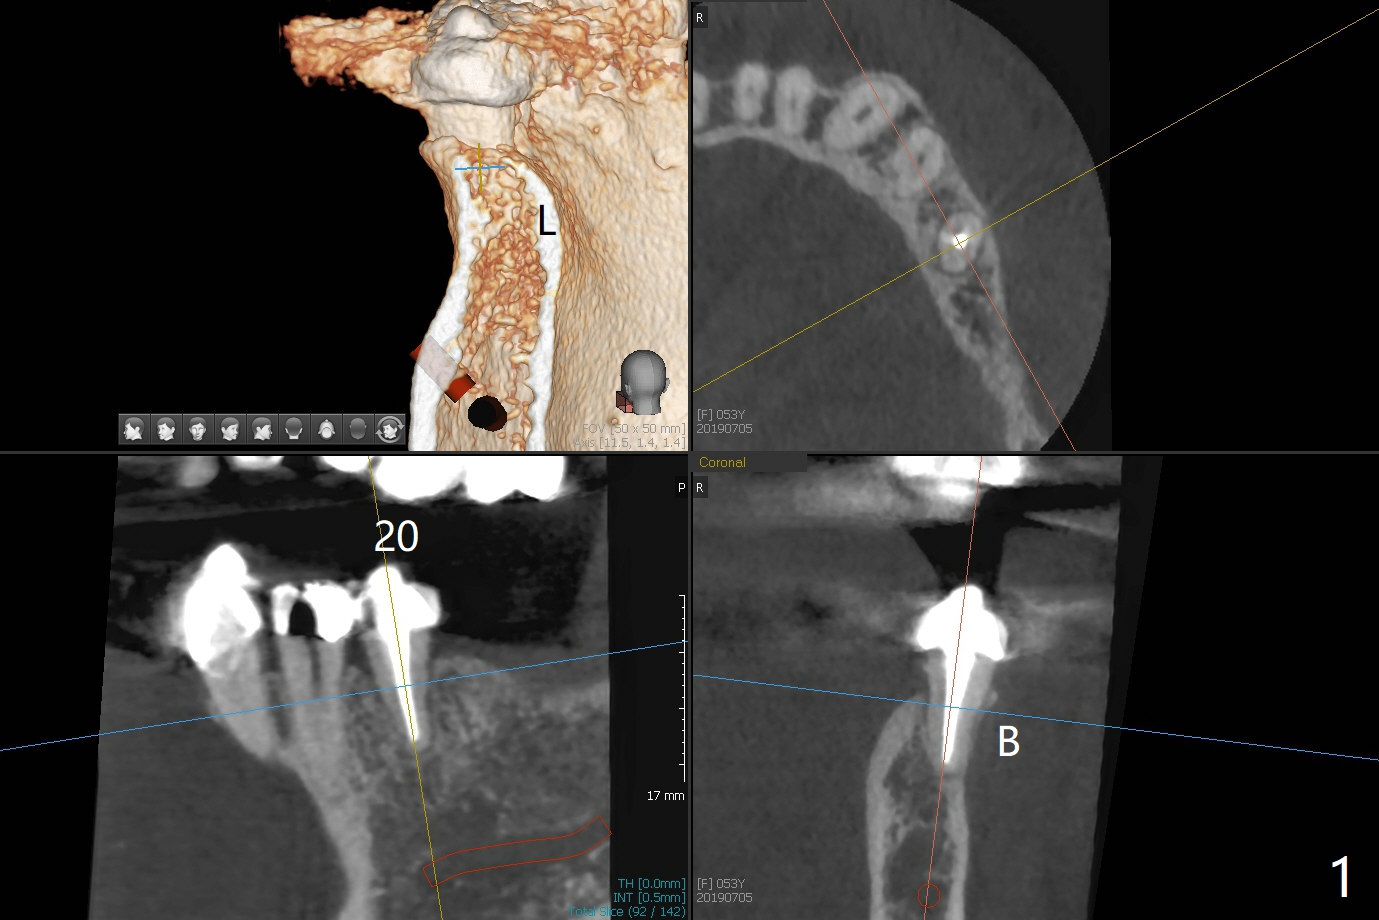

A 53-year-old woman develops an abscess lingual to the tooth #20 before #19 final restoration. Reanalysis of CT taken 5 months earlier shows the thin buccal plate (Fig.1 B). A 3.5x13 mm bone-level/3.5x17 mm tissue-level implant should be lingually placed (Fig.2,3). Socket shield will be performed (Fig.4 *); the lingual cortex removed with Lindamann bur (red) for ~1.6 mm. Initial osteotomy will be conducted in the lingual wall of the socket coronally (Fig.5 white arrow); after penetration, the initial drill will change the trajectory (Fig.6).